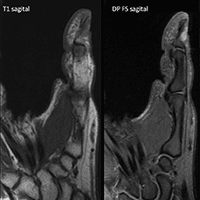

Paciente do sexo feminino, 47 anos, com lesão nodular dolorosa subungueal no I dedo há meses. Relata aumento da sensibilidade nesta região, especialmente no frio.

Imagens